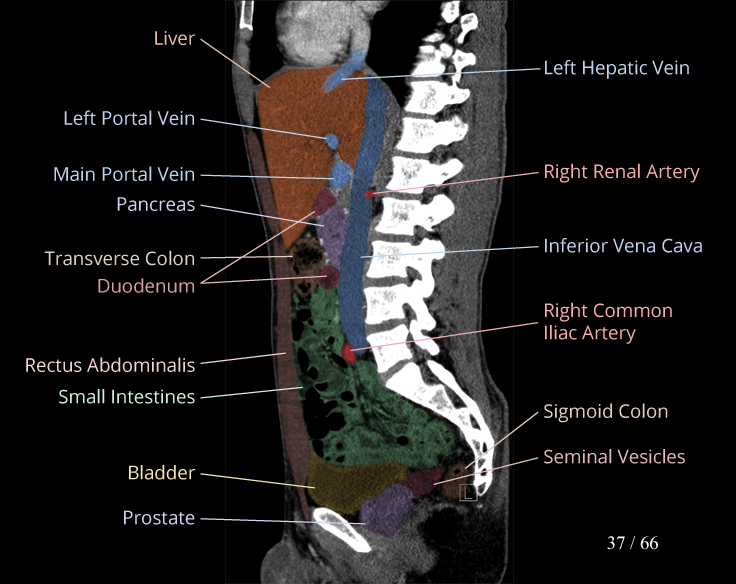

Body

Covers abdominal CT anatomy.